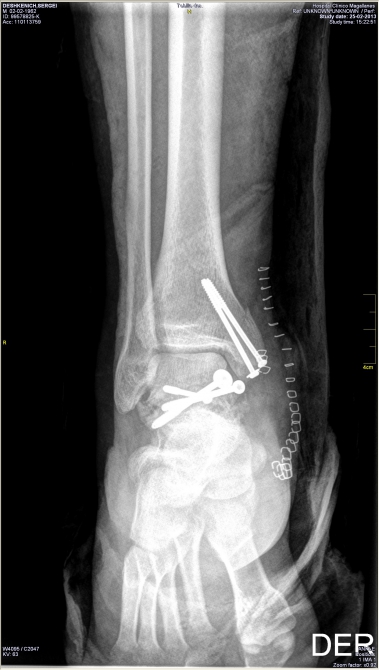

А дальше: бесконечный спуск, попытки вызвать вертолет, разборки со страховой (можно написать отдельную статью про мытарства), госпиталь, операция, длительное восстановление... Диагноз — перелом со смещением таранной кости и осколочно лодыжки. Что будет дальше? Поживем — увидим.